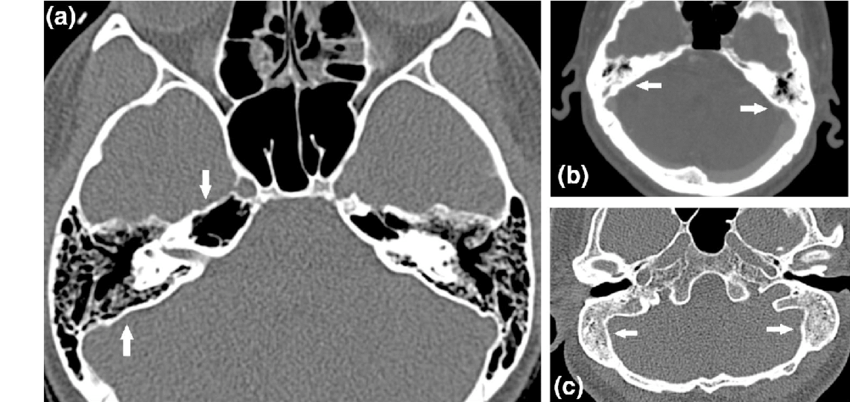

副鼻腔炎は急性と慢性に分かれ、慢性副鼻腔炎ではCTによる含気腔の透過性変化を評価することが診断の鍵になります。

特に前頭洞や上顎洞の骨折では、視覚や嗅覚への影響を伴うことがあるため、画像診断による早期評価が不可欠です。

CT・MRI画像での含気骨の見方

含気骨は空洞(含気腔)を持つ構造のため、画像上では“黒く抜ける”部分として認められ、骨・粘膜・液体の変化によって明らかに異なる所見を呈します。画像を読む際には以下の点がポイントになります。

まず、基本的な見え方と確認すべきポイントを整理します。

- 含気腔の典型的所見:骨〜空気〜軟組織の陰影変化

↳空気=低吸収(CTでは黒に近い)、骨=高吸収(白に近い) - 左右対称・形状・大きさの確認

↳正常では左右に大きな差がないことが多いが、個人差あり - 異常所見のチェック項目:

・粘膜肥厚/液体貯留(含気腔内に液体やムチンが入ると灰色〜白っぽく写る)

・骨壁の破壊・骨変形(慢性炎症や腫瘍で起こりうる)

・開口部の狭小化・閉塞(鼻腔、副鼻腔道の交通障害)

例えば、乳突蜂巣(側頭骨内の含気腔)を薄層CTで観察すると、含気化の程度が術前リスクの指標になるという報告があります。 また、上顎洞(上顎骨にある含気腔)では、慢性副鼻腔炎の際、粘膜肥厚・液体貯留・骨肥厚がCT上明らかになります。 こうした所見を系統的にチェックできるよう、画像を読む習慣をつけることが重要です。